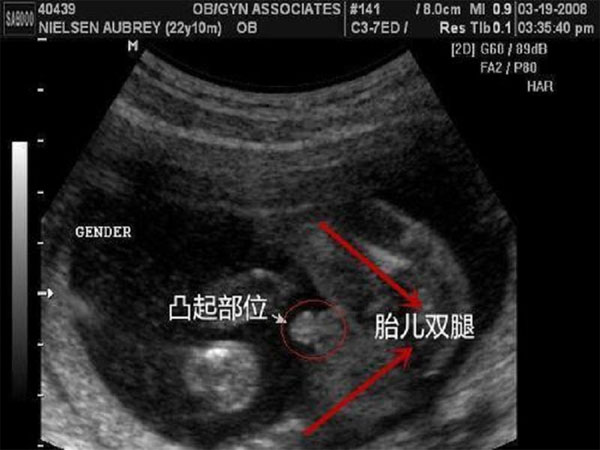

1、NT检查时男孩和女孩的生殖器形状是一样的,但是男孩的特征点与身体呈45度角,还多一些,女孩的特征点几乎是和躯体平行的,一般不会超过30度。

2、男宝宝的屁股位置会微微上翘,后背脊柱成圆弧状,因为要留空间发育前列腺,相反,女宝宝后背脊柱就相对就平一些。

2、检查时胎儿在子宫内的姿势不同和超声波照射的方位不同,在b超检查单子上胎儿的尾椎骨末端和小腹之间的突出点方向也不同,所以通过nt检查看男女是没有科学依据的。